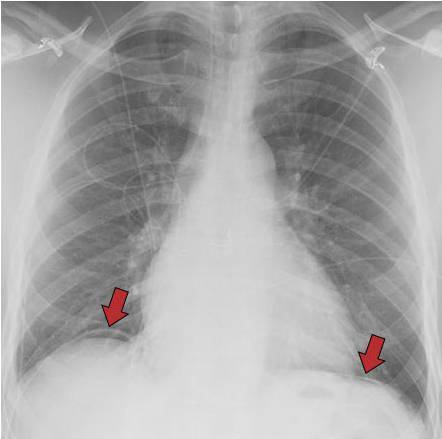

正常人的胸片模板,正常胸片和异常胸片

正常胸片和异常胸片

胸片正常图片

正常胸片

正常胸片影像图片